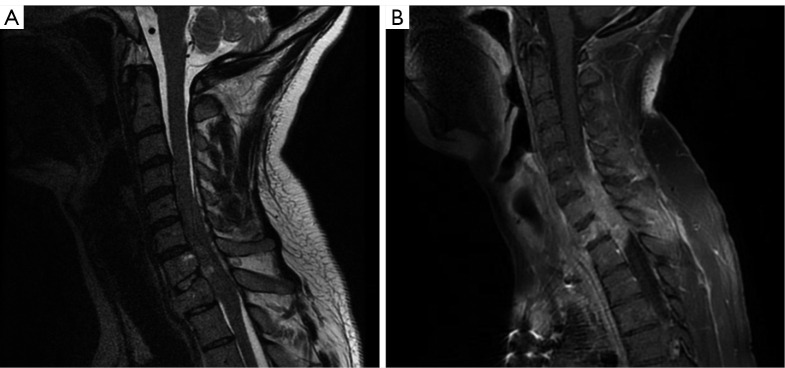

Case description: A 28-year-old male with a history of YST presented to our institution with urinary retention, increasing weakness in the upper extremities, and acute onset lower extremity weakness. Computed tomography (CT) and magnetic resonance imaging (MRI) scans confirmed evidence of metastasis from a known YST with symptomatic cord compression. The patient was treated with surgical excision via decompressive laminectomies with instrumentation as described, and histopathologic analysis of the specimen confirmed YST metastasis. His disease recurred one year after index surgery. He succumbed to his disease despite repeated debulking.